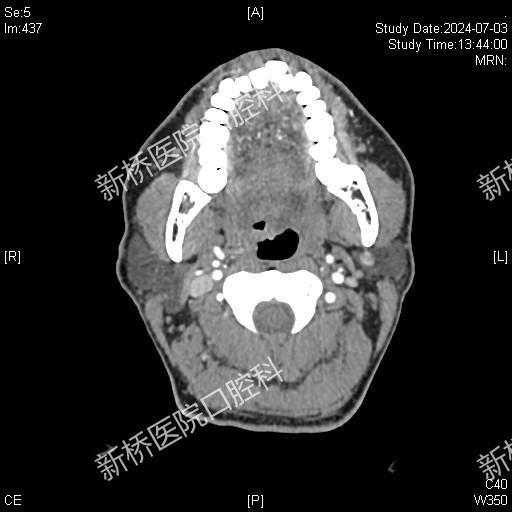

经口腔治疗口咽部、喉部、甚至咽下部区域的手术,因解剖结构复杂、视野严重受限,临床上操作难度极大。经口机器人手术(Transoral robotic surgeryTORS)是经口腔手术技术上的革新,属于内镜经口腔手术的一种。其利用带角度镜头臂伸入口内,使得上述部位放大的3D影像完整呈现于术者眼前,获得视野更宽广,更清晰,更逼真的深部